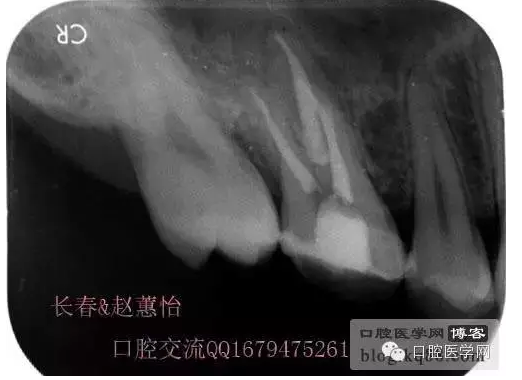

看多了文字眼花繚亂了吧,今天一個根管內(nèi)有臺階的患牙被充填上了,刻意投照了N多的X光片終于有一個給力的了,仔細觀察,可以看得見喔,也算是辛苦努力給個安慰獎,很多都是從片子上看不出有什么不同的。

這個是術(shù)前照片,一切如常

患牙是死髓牙,患者是一位大學(xué)生,探查根管時一切都很順利,就有點忽視了,當然這個臺階是人為造成的,造成的原因呢就是使用機擴時跳號了,所以大家一定要逐號使用啊,預(yù)備出一個臺階,后續(xù)要搭上很長時間才能搞定,好不容易越過臺階下去的銼,一提拉出來就下不去了,著實讓人郁悶,一切都要從頭再來,這個時候再下銼的時候就必須預(yù)彎了。而且要多角度試探,很是考驗?zāi)托牡臅r候。吃一塹長一智嘛!

術(shù)后,明顯可見近中頰側(cè)根管臺階位置

越過臺階后小心預(yù)備直至大錐度銼可以順利進術(shù)前片的小彎沒當回事,哎